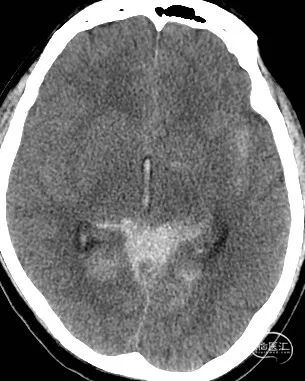

影像检查:CT提示广泛蛛网膜下腔出血(环池、四叠体池、桥前池、桥小脑角、三脑室),Fisher分级2级。CTA提示左侧大脑后动脉P2段动脉瘤,大小约2.3mm*1.3mm,颈宽约2.3mm。

DSA结果:左侧P2段动脉瘤,约1mm*0.8 mm,颈宽约0.8mm,形态不规则。

影像检查:CT提示广泛蛛网膜下腔出血(环池、鞍上池、桥前池、侧裂池、侧脑室),Fisher分级3级。CTA提示右侧颈内动脉交通段动脉瘤。

DSA结果:右侧颈内动脉后交通段动脉瘤, 7.2mm*6.7mm*5.7mm,瘤体上多个小子囊,载瘤动脉异常扭曲及不规则狭窄,直径约4.2mm。

术前DSA、DSA 3D